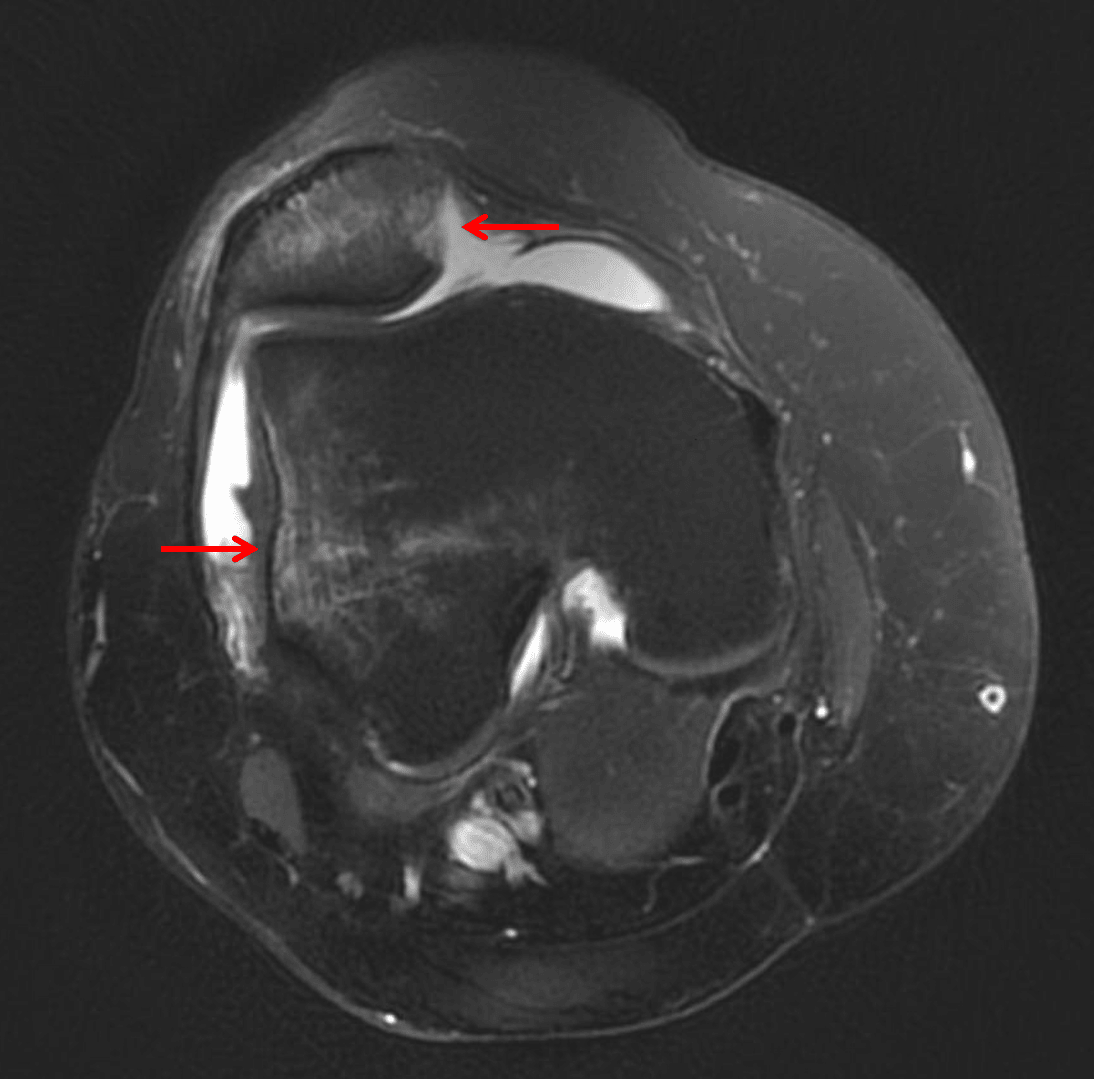

Sequela of lateral patellar dislocation. MRI in this patient shows kissing contusions in the medial patella and lateral femoral condyle (red arrows).

• MRI often shows a “kissing contusion” pattern with bone contusions along the medial patella and lateral femoral condyle at the sites of impact